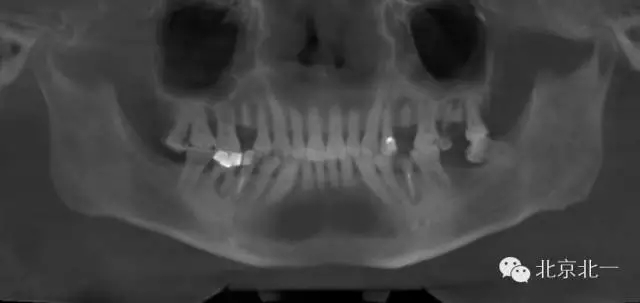

1.難度預(yù)判:拔牙前了解需拔除患牙情況及其與鄰牙、周圍組織的關(guān)系 術(shù)前影像學(xué)檢查了解牙齒形態(tài)、結(jié)構(gòu)及其與周圍重要解剖結(jié)構(gòu),如上頜竇、下頜神經(jīng)管等的位置關(guān)系。術(shù)前與患者及家屬交代拔牙過(guò)程及術(shù)中、術(shù)后的相關(guān)事項(xiàng),以緩解患者的緊張、恐懼心理,取得其信任與配合。

其他區(qū)域埋伏牙(多生牙、尖牙、前磨牙、上頜第三磨牙)首先根據(jù)影像學(xué)選擇正確的手術(shù)人路,翻瓣及去除覆蓋牙冠骨組織,顯露患牙牙冠,然后通過(guò)增隙或分割,遵循“化整為零”的微創(chuàng)理念取出患牙。